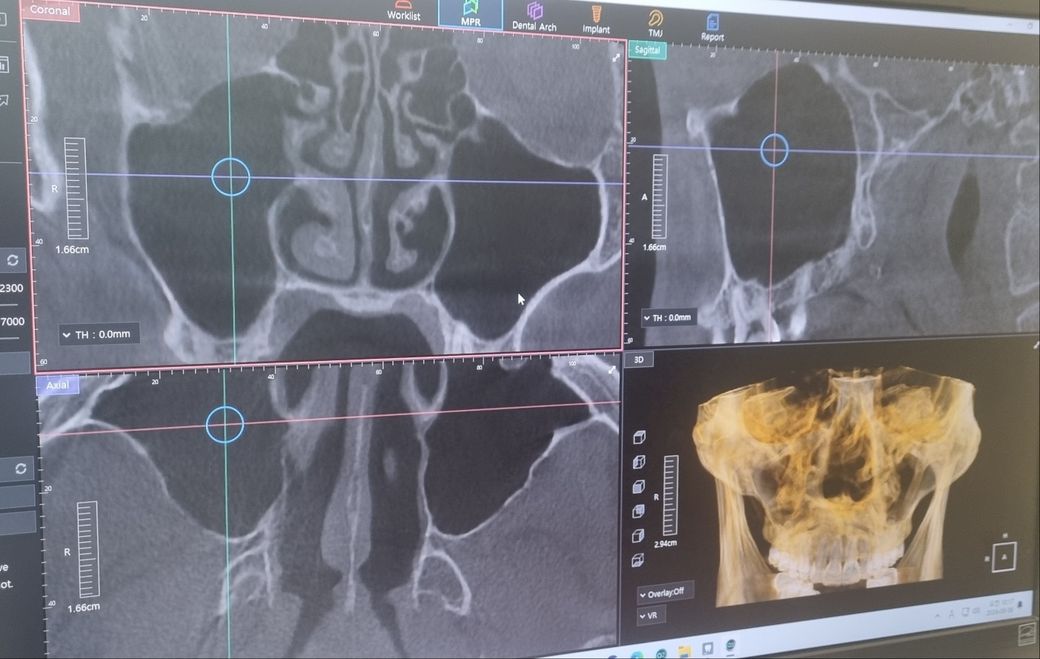

이게 치과가서 ct나 엑스레이를찍어보니까 별문제는없는데 혹시 비염있냐고 물어보시더라고요 근데 제가 콧물은잘안나고 코가 좀막힌듯한 증상이있는데 이것도 비염중에 있는 증상이라고하더군요

치과에서는 자세히는 모르는데 ct상 비염인지 부비동염인지 의심간다고 해서 일단 이빈후과가보라는데

혹시 ct사진중에 비염에 의심갈만한게 보이는지 궁금합니다 사진이 깔금하게 안나온점은 죄송합니다

• 2번 째 사진

올려주신 사진에서 부비동에 염증 소견은 저명하지 않으나 오른쪽 코 점막이 부어 있어 비염의 가능성이 생각됩니다.

불편증상이 있다면 이비인후과 진료를 바랍니다.